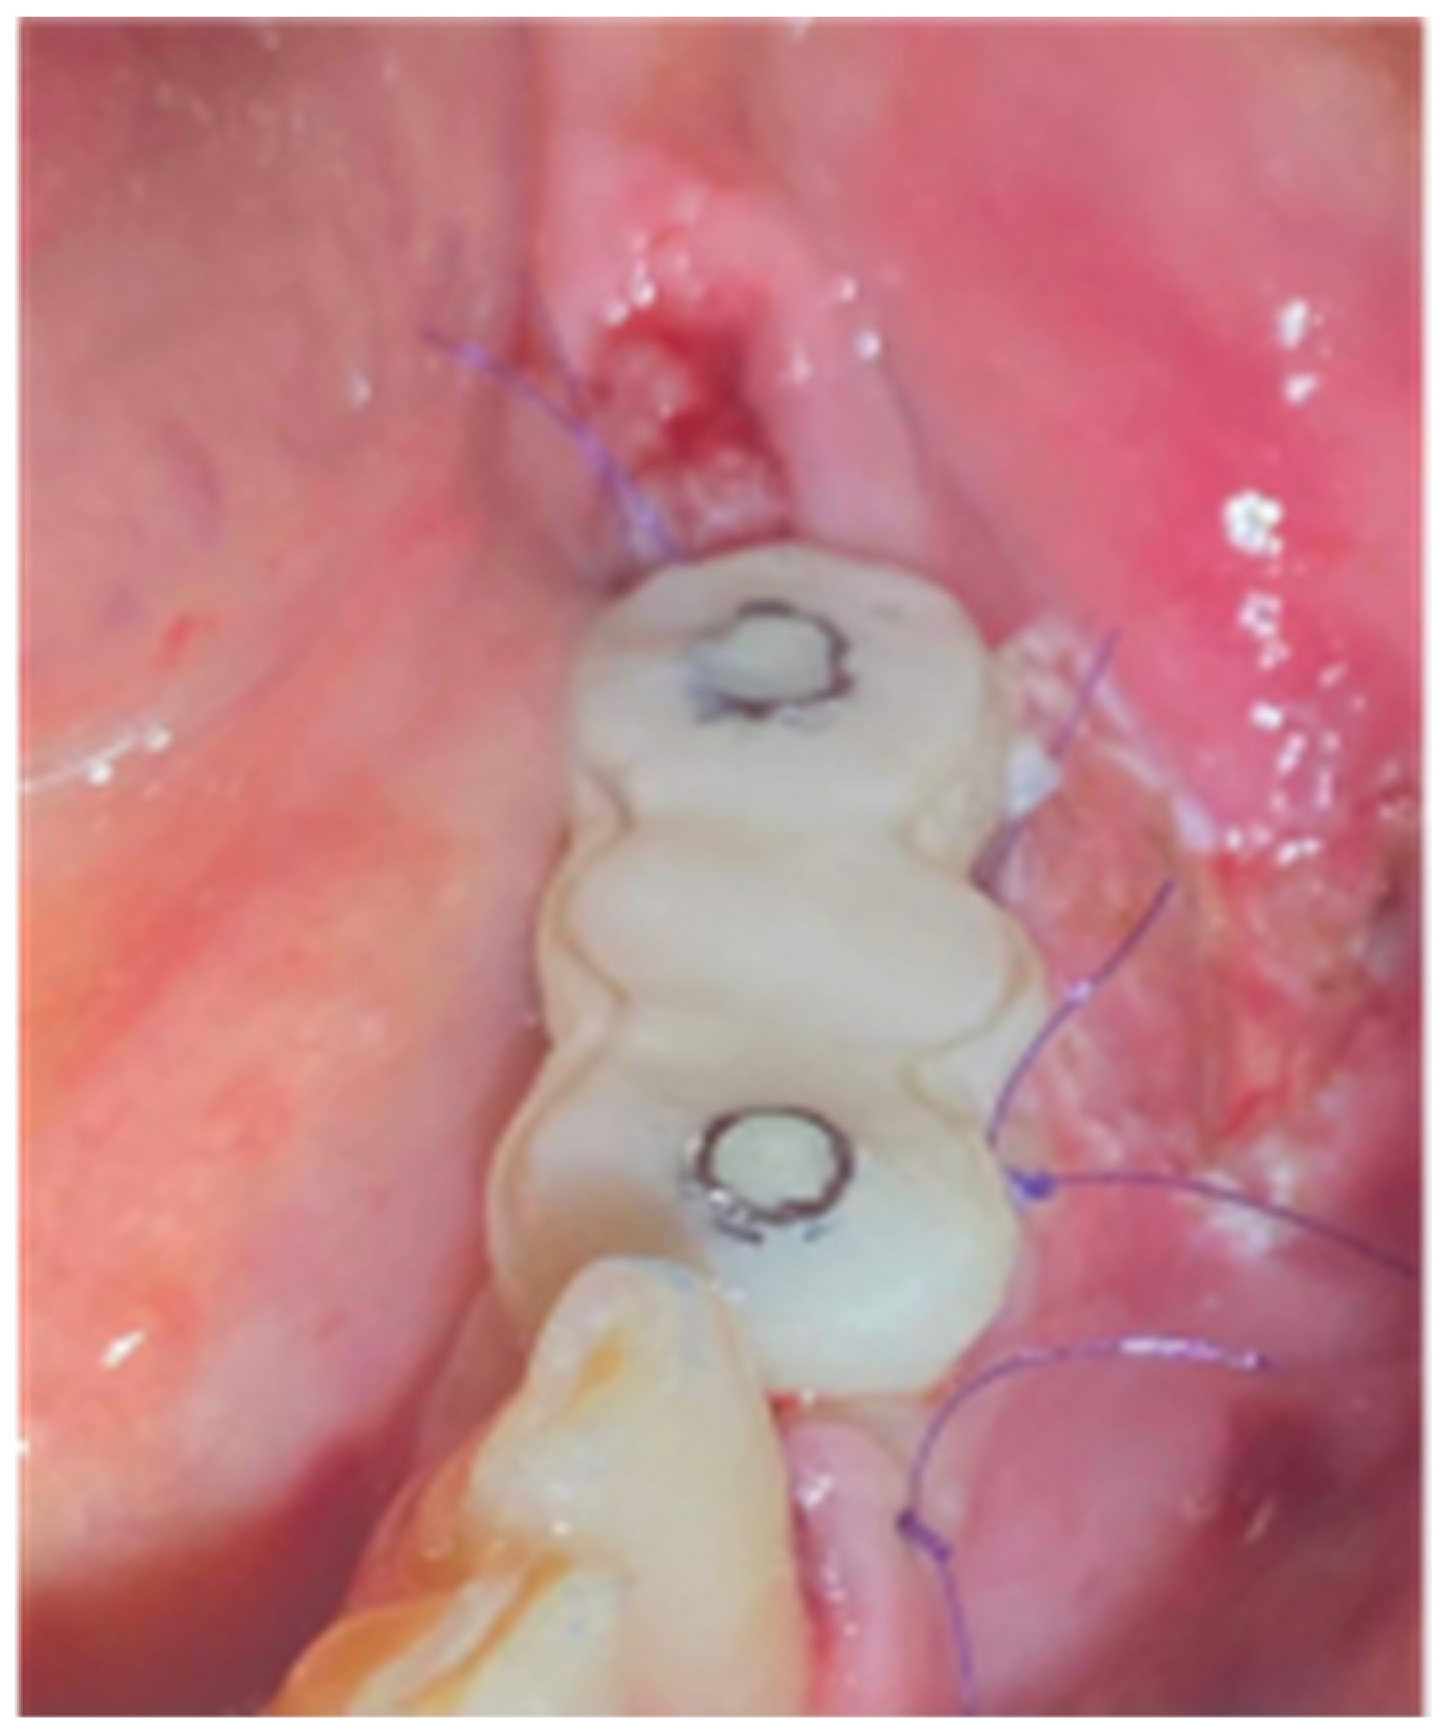

2.3. Stage 2

2.6. Stage 2